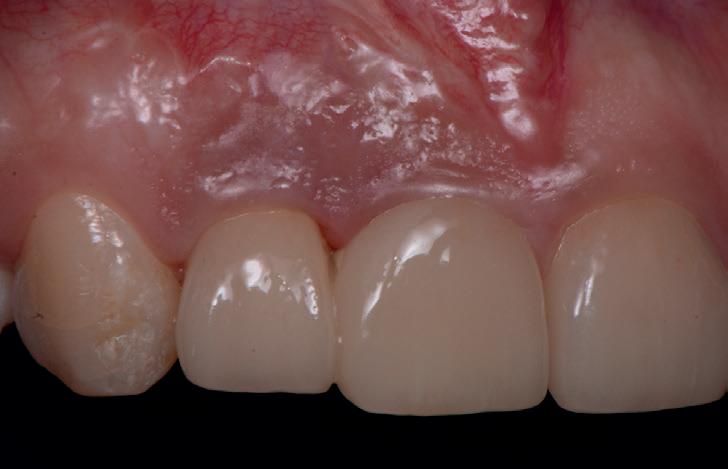

SITE AUGMENTATION Reconstituirea țesutului moale periimplantar și papilar în zona estetică

RECONSTITUIREA țesuturilor moi periimplantare. Scopul acestui raport de caz este de a demonstra procedurile chirurgicale utilizate pentru corectarea unui defect al țesuturilor moi periimplantare folosind țesutul moale interdentar în combinație cu tuberozitatea ca locație donatoare de țesut conjunctiv, utilizând o abordare prin tunelizare într-o zonă estetică.

Totuși, ca și în cazul implanturilor de titan, în rare cazuri, și la cele ceramice poate apărea o recesie nedorită cu expunerea umărului implantar. Cu toate acestea, din punct de vedere estetic, această recesie a gingiei inflamate este posibil să fie mult mai bine tolerată de către pacienții preocupați de marginile întunecate ale implanturilor de titan (fig. 2).

În plus, aceste proprietăți bioinerte par să aibă și beneficii în ceea ce privește dezvoltarea periimplantitei și calitatea țesuturilor moi. În comparație cu titanul, dioxidul de zirconiu prezintă acumulare de placă și aderență bacteriană mai redusă, precum și o grosime mai mică a biofilmului depus. Și fluxul sanguin circulant către țesuturile moi este mai asemănător cu cel al unui dinte natural în cazul ceramicii față de titan, care oferă flux sanguin redus semnificativ. Se știe că o circulație sanguină mai bună înseamnă țesuturi moi mai sănătoase, care, la rândul lor, prezintă rezultate estetice îmbunătățite. Deși deocamdată lipsesc dovezile pe termen lung pentru implanturile ceramice, sunt disponibile rezultatele inițiale la 3 și 5 ani, iar tendința, susținută de studii preclinice și experiența clinică, este că dioxidul de zirconiu demonstrează același rezultat - iar în unele studii chiar o pierdere osoasă marginală mai redusă față de implanturile de titan. În această perioadă încă nu s-a descris clinic periimplantită.

Trebuie remarcat, totuși, că în cazul implanturilor ceramice, ca și în al celor de titan, cementita, adică inflamația periimplantară cauzată de reziduurile de ciment, poate duce la periimplantită. În plus, la implanturile din dioxid de zirconiu poate apărea supraîncălzirea la înșurubarea implantului în os, iar suprafețele excesiv de aspre sau poroase ale implantului pot cauza defecte osoase periimplantare din cauza termoconductivității reduse a materialului. Deși sunt necesare mai multe dovezi științifice care să demonstreze o tendință mai scăzută spre periimplantită în cazul implanturilor ceramice, argumentul esențial pentru aceste implanturi bazat pe experiența clinică este starea excelentă și aproape constant lipsită de inflamație a țesuturilor moi periimplantare (fig. 3).